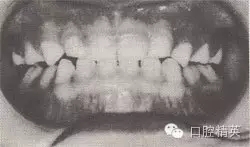

患者,男,4歲,乳牙。磨牙近中關(guān)系。前牙反頜,下頜前突,位置前移。

診斷:乳前牙反頜,安氏Ⅲ類,毛氏Ⅱ¹。

矯治設(shè)計:上頜頜墊式活動矯治器。下頜后退位解剖式頜墊,舌簧推乳上切牙向唇側(cè),調(diào)磨頜墊。

治療時間:1.5個月,乳前牙反頜解除,乳切牙達到正常覆頜、覆蓋。下頜回到正常位置。

圖8-37 安氏Ⅲ類錯頜,乳前牙反頜矯治前后面頜像

矯治前面相